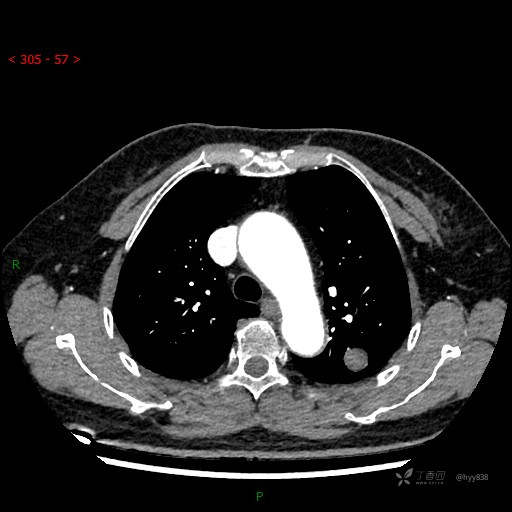

增强动脉期

各期CT值:28hu、58hu、69hu